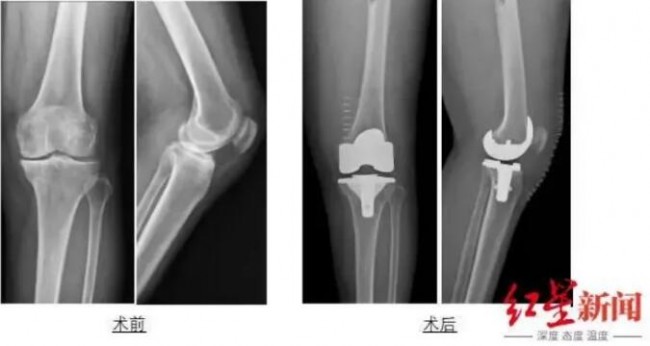

9月30日下午,周宗科教授团队成功为吴婆婆施行了左膝关节置换术。术中植入生物型膝关节假体时无需骨水泥对假体进行固定,手术时间得到明显缩短。术后X线片显示,假体与骨完美匹配,固定良好,位置正常,吴婆婆左膝畸形得到完全纠正,膝关节活动度好。困扰患者多年的膝盖问题最终得到解决。